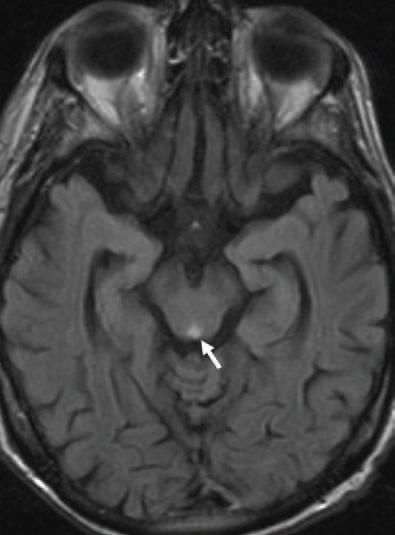

To further evaluate his neurological deficits, MRI of the brain was performed. An increased signal within the pons with a central focus of restricted diffusion was described (Figure 4).

Further review of the MRI scan of the brain revealed that the pontine lesion appeared more vascular in nature than infectious. Our patient was treated with a combination of isoniazid, 300 mg; rifampin, 600 mg; and ethambutol, 25 mg/kg (1300 mg), orally every day. He was discharged to a subacute-care facility with follow-up arranged in our outpatient clinic.